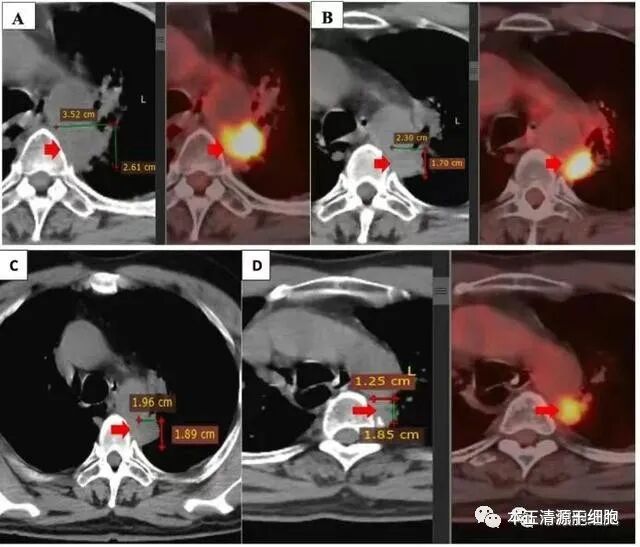

图3。联合治疗前后的原发性肿瘤。原发性肿瘤在二线治疗后进展(4个周期的阿力玛、卡铂、凯曲达)(A)。联合NK细胞治疗、吉西他滨、贝伐单抗(B)、3个月后(C)和6个月后,原发性肿瘤在治疗结束时减少(D)。

两次复查PET/CT影像显示原发病灶明显缩小(上图B和D)。并且,纵膈淋巴结和双侧锁骨上淋巴结的转移灶也都消失了。